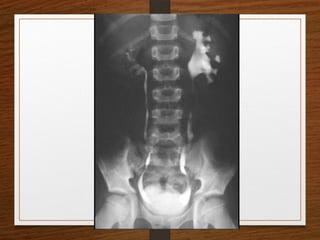

4. Renal Caluculus

5. Bladder Calculus

What are the D/D of a radiopaque shadow in this region?

• Kidney stone

• Gallstones

• Pancreatic calculi

• Foreign body

• Fecolith

• Phleboliths

• calcified lymph node

• calcified renal tuberculosis

• calcified adrenal gland

• chip fracture of a transverse process of vertebra or calcification of costal

cartilage

What are theD/D of a radiopaque shadow in this region? • Kidney stone • Gallstones • Pancreatic calculi • Foreign body • Fecolith • Phleboliths • calcified lymph node • calcified renal tuberculosis • calcified adrenal gland • chip fracture of a transverse process of vertebra or calcification of costal cartilage